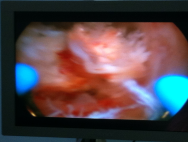

诊疗过程:入院后完善相关辅助检查,予以在腰麻下行宫腔镜电切术:患者取膀胱截石位于手术台上,腰麻成功后,碘伏常规消毒会阴部手术野皮肤及阴道,妇科检查:外阴已产式,阴道畅,分泌物少,无异味,宫颈轻度糜烂,无举痛。子宫常大,无压痛。双附件未及明显异常。探宫腔225px,用20%甘露醇作膨宫液行宫腔镜检查术,宫腔形态规则,宫腔内右后壁近输卵管开口处见4.0*2.5*50px胎盘机化绒毛样肿物突起,内膜少,两输卵管开口清晰可见,宫颈管形态正常,用环形电极行电切术,术中见深达肌层。符合“胎盘植入”。充分止血后。检查宫腔形态正常。术毕。切除物送病理检查:坏死组织中有少许子宫内膜及钙化、机化组织。